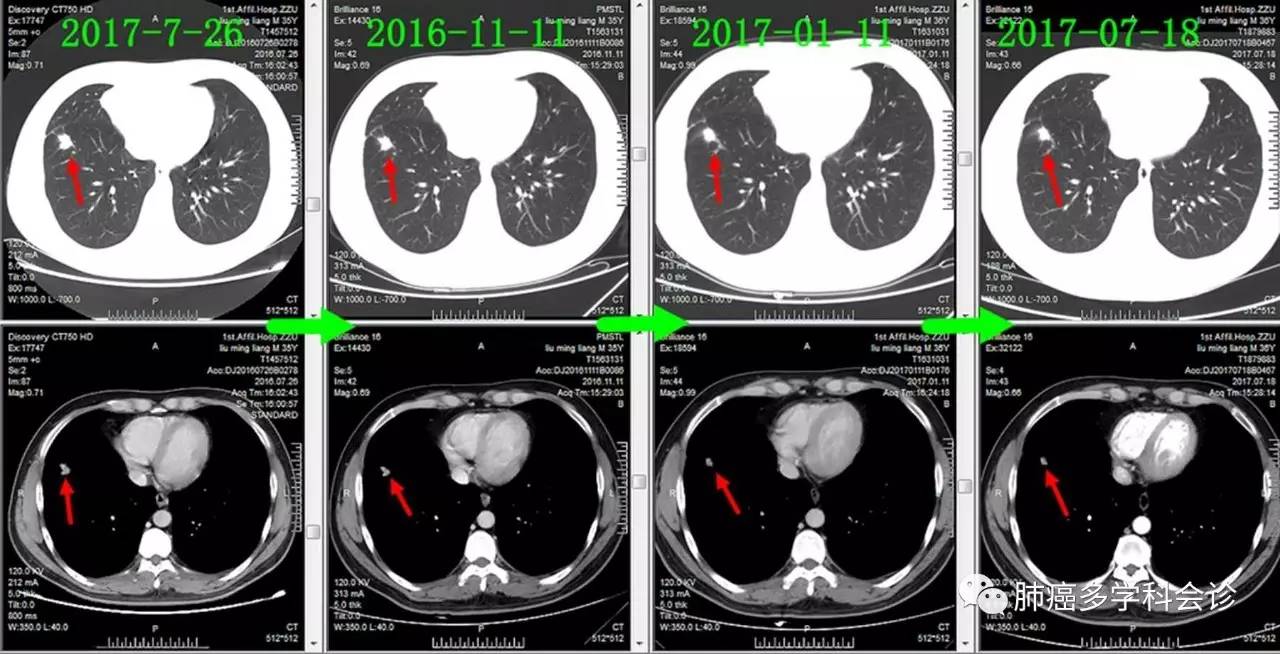

下面通过对比治疗过程中胸部CT变化,展示胸部肿瘤此消彼长的过程:

肺原发灶略有缩小

纵隔肿大淋巴结逐渐缩小

胸膜转移灶消失

-